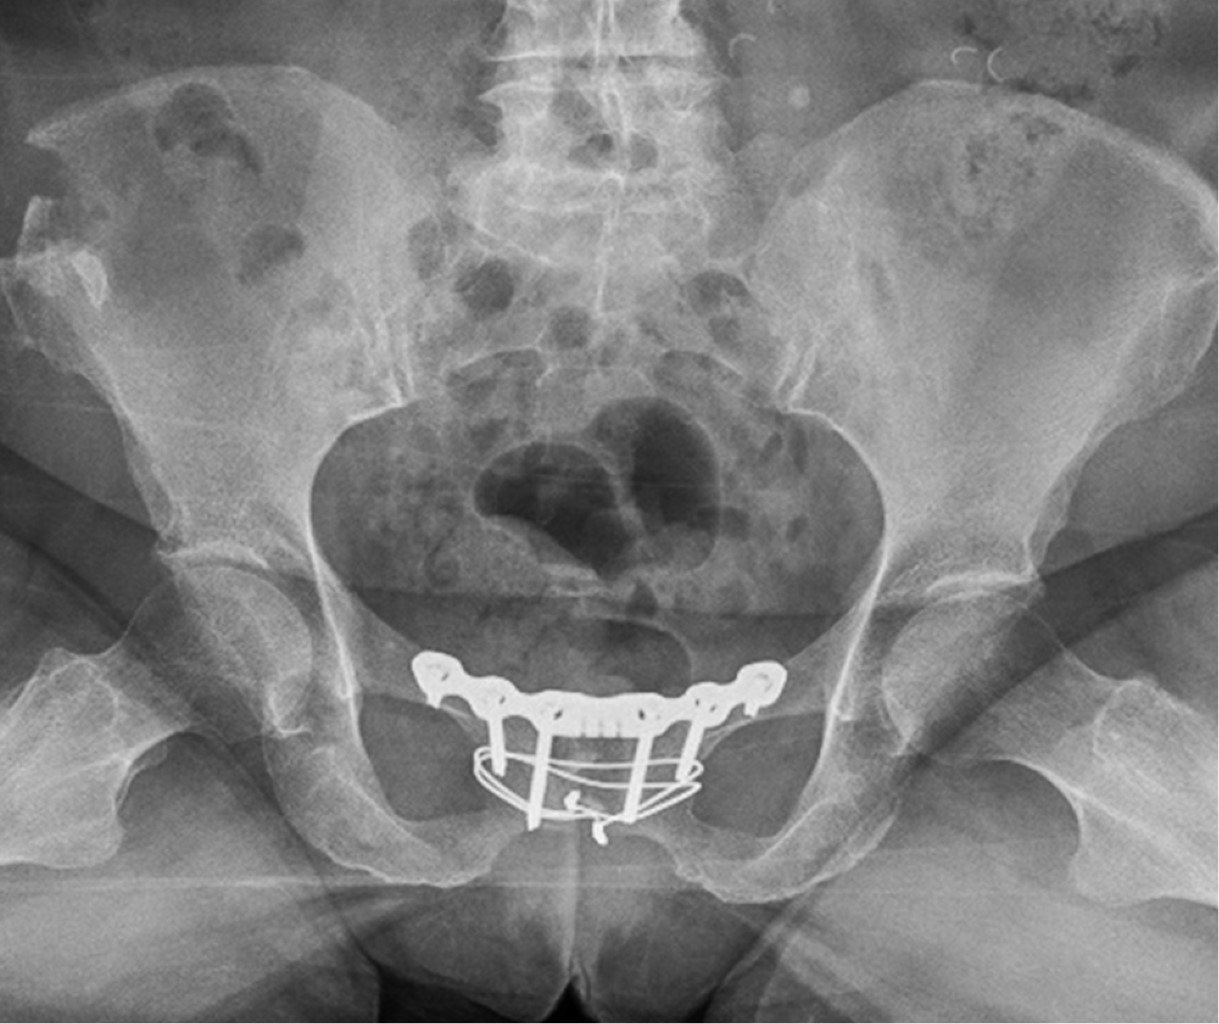

Ambas pacientes fueron mantenidas en descarga durante cuatro semanas, con autorización para carga parcial a partir de la cuarta. Se sometieron a revisiones ambulatorias trisemanales, durante las cuales se observó una reducción escalonada de la analgesia y un aumento en la autonomía para las actividades diarias. En las revisiones, se realizaron radiografías en proyección anteroposterior y en carga (Figuras 8 y 9). A las 12 semanas, iniciaron ejercicios moderados sin impacto. El dolor significativo en la sínfisis del pubis, que inicialmente impedía la deambulación, se redujo gradualmente hasta su completa desaparición, con puntuaciones de 1 en la EVA. No se requirió la retirada del material de osteosíntesis en ninguna de las pacientes durante el seguimiento hasta el momento actual tras dos años de seguimiento.

Figura 8

Figura 9